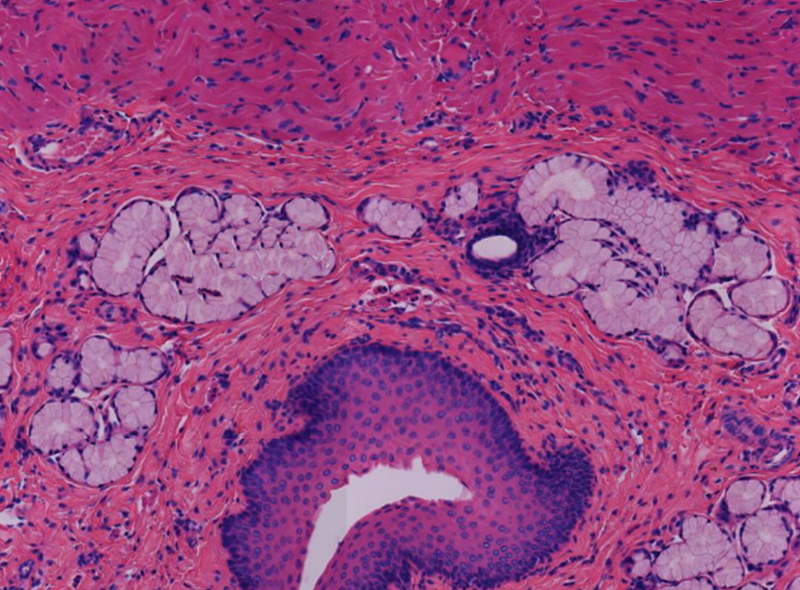

支氣管擴(kuò)張